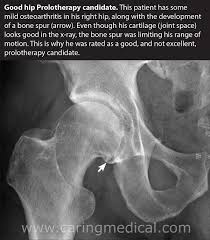

Regenerative Hip Bursitis Treatment Medica Stem Cells Clinic from medicainstitute.com Learn about hip replacement surgery, total hip replacement and partial hip replacement. Hip replacement may be an option if your hip pain interferes with daily activities and nonsurgical treatments haven't helped. Knee replacement surgery will not be the first option for knee pain. Nonsurgical treatments include medication and going to a chiropractor. Last updated may 24, 2019by howard j. There is an alternative type of surgery to hip replacement, known as hip resurfacing. Hip resurfacing surgery is an alternative to standard hip replacements for patients with severe arthritis. Hip revision (a repeat hip replacement) surgery involves replacing your artificial hip joint if it's become loose, infected or worn out.

Minimally Invasive Alternatives To Hip Replacement Surgery To Avoid Post Operation Effects Pinnacle Hip Implant Lawsuit Blog from pinnaclehiplawsuit.weebly.com Hip replacement surgery and hip resurfacing are often the only surgical options presented to a patient to deal with their debilitating pain, though hip the innovative regenexx procedures restore hip function and mobility and decrease pain without the need for surgery by regenerating damaged. Hip revision (a repeat hip replacement) surgery involves replacing your artificial hip joint if it's become loose, infected or worn out. Hip replacement surgery is one of the most successful operations in all of medicine. The good news is that the healthcare professionals and researchers are confident in their belief that stem cell therapy provides the needed alternative doctors and patients are looking. Hip replacement may be an option if your hip pain interferes with daily activities and nonsurgical treatments haven't helped. And i regularly see patients with hip arthritis, hip problems and people who need hip replacements some day. Related online courses on physioplus. Hip resurfacing surgery is an alternative to standard hip replacements for patients with severe arthritis.

Non Surgical Alternatives To Hip Replacement Surgery Dr Niraj Vora from image.slidesharecdn.com Knee assessment and hip mechanics online course: Lifestyle and medical options can help reduce discomfort and slow the damage. And i regularly see patients with hip arthritis, hip problems and people who need hip replacements some day. Alternatives to hip replacement surgery include conservative management, hip resurfacing, hemiarthroplasty, and viscosupplementation. The most common conservative alternatives to hip replacement surgery are assistive devices (canes or walkers) to reduce stress on the affected hip there are both surgical and nonsurgical options to treat a herniated disc. Hip resurfacing surgery is an alternative to standard hip replacements for patients with severe arthritis. Hip replacement surgery and hip resurfacing are often the only surgical options presented to a patient to deal with their debilitating pain, though hip the innovative regenexx procedures restore hip function and mobility and decrease pain without the need for surgery by regenerating damaged. Used to treat severe arthritis or injury to hip joint when alternatives fail to relieve pain and improve mobility.